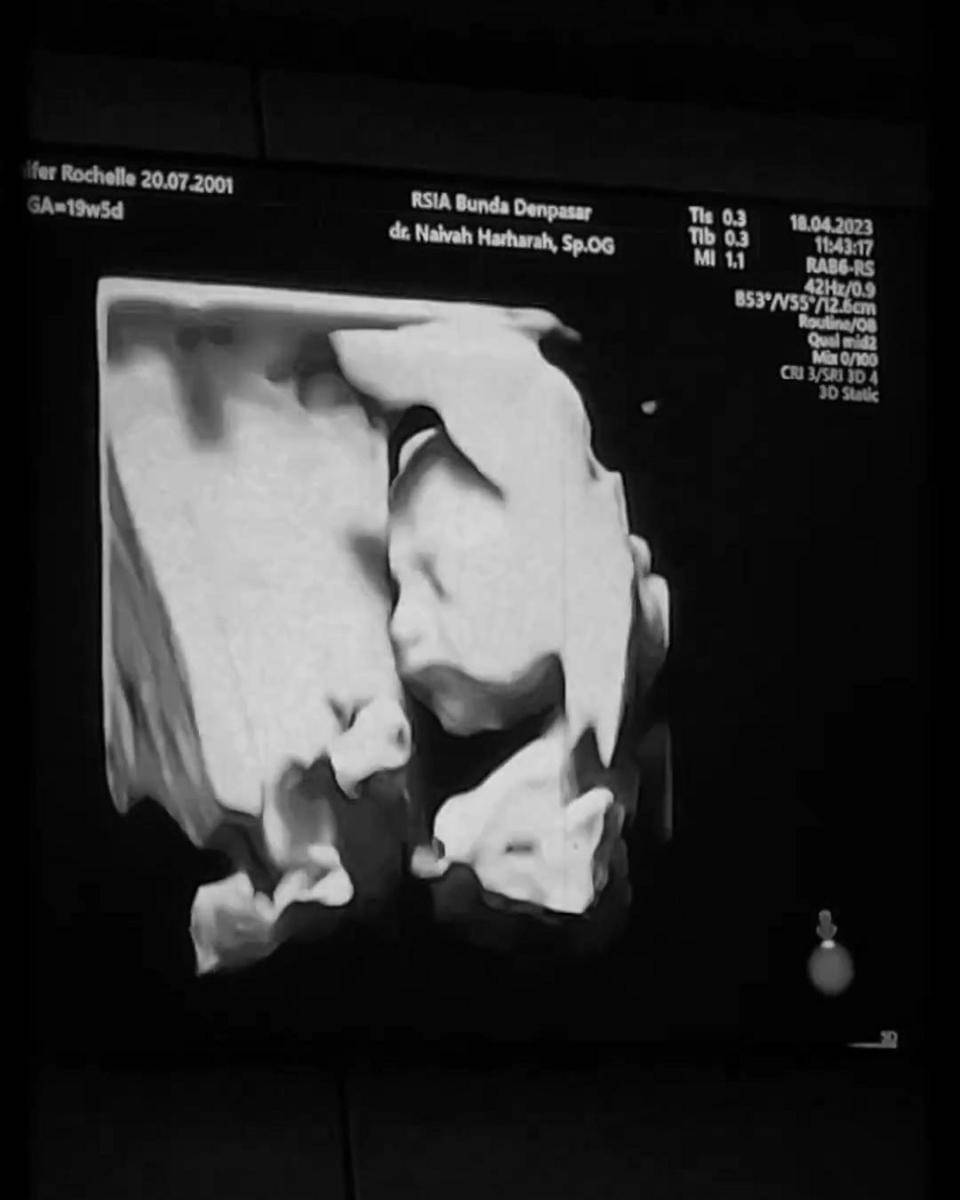

Pesinetron Jennifer Coppen mendadak menjadi perbincangan banyak orang usai mengumumkan tentang kehamilannya.

Melalui akun Instagram pribadinya, perempuan berusia 21 tahun itu memberi tahu bahwa ia tengah hamil dengan usia kandungan 23 minggu dan tiga hari.

"23 minggu dan 3 hari selama itu aku sudah mengandung malaikat kecil di perutku. Sudah selama itu aku menyimpan kabar ini untuk diri sendiri dan merahasiakannya dari publik. Butuh waktu 23 minggu dan 3 hari buat aku untuk cukup berani dan akhirnya siap untuk membagikan berita ini ke seluruh dunia," tulisnya dalam akun Instagram @jennifercoppenreal20, Minggu (14/5/2023).